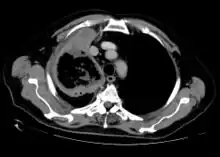

Imaging

Imaging is often performed, such as CT scan of lungs and sinuses.[38] Signs on chest CT scans, such as nodules, cavities, halo signs, pleural effusion and wedge-shaped shadows, showing invasion of blood vessels may suggest a fungal infection, but does not confirm mucormycosis.[16] A reverse halo sign in a person with a blood cancer and low neutrophil count, is highly suggestive of mucormycosis.[16] CT scan images of mucormycosis can be useful to distinguish mucormycosis of the orbit and cellulitis of the orbit, but imaging may look identical to those of aspergillosis.[16] MRI may also be useful.[39]

CT scan chest of person treated for acute myeloid leukaemia, presented with cough, fever and shortness of breath.